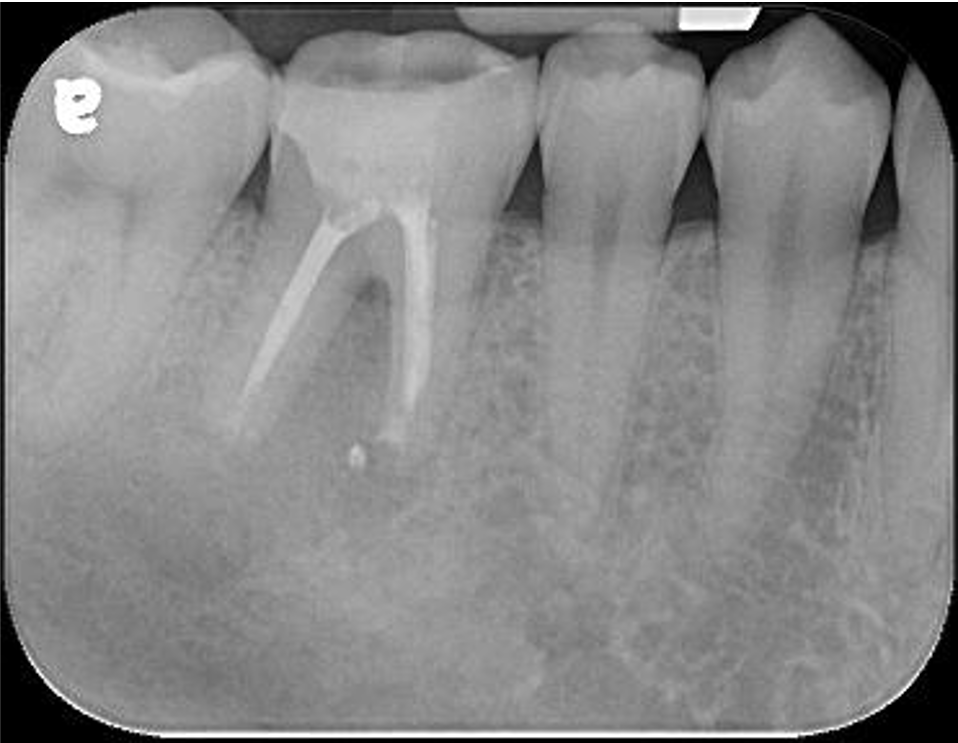

治療前,蛀牙與根尖破壞

先進行非手術顯微根管治療

牙齒拔出,刮除根尖病變

6個月後,根大病變癒合